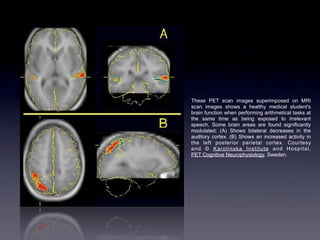

The sculpture "The Short, Rich Life of Positronium" commemorates fundamental research on antimatter conducted at the University of Michigan. Positron emission tomography (PET) uses positron-emitting radioactive isotopes as tracers and coincidence detection of the resulting back-to-back photons to construct tomographic images. PET enables visualization of functional processes in the body by tracking radioactive tracers like fluorodeoxyglucose, which is used to show glucose metabolism and thus tissue activity. While providing valuable medical information, PET also involves some radiation risks due to the penetrating nature of the emitted photons.